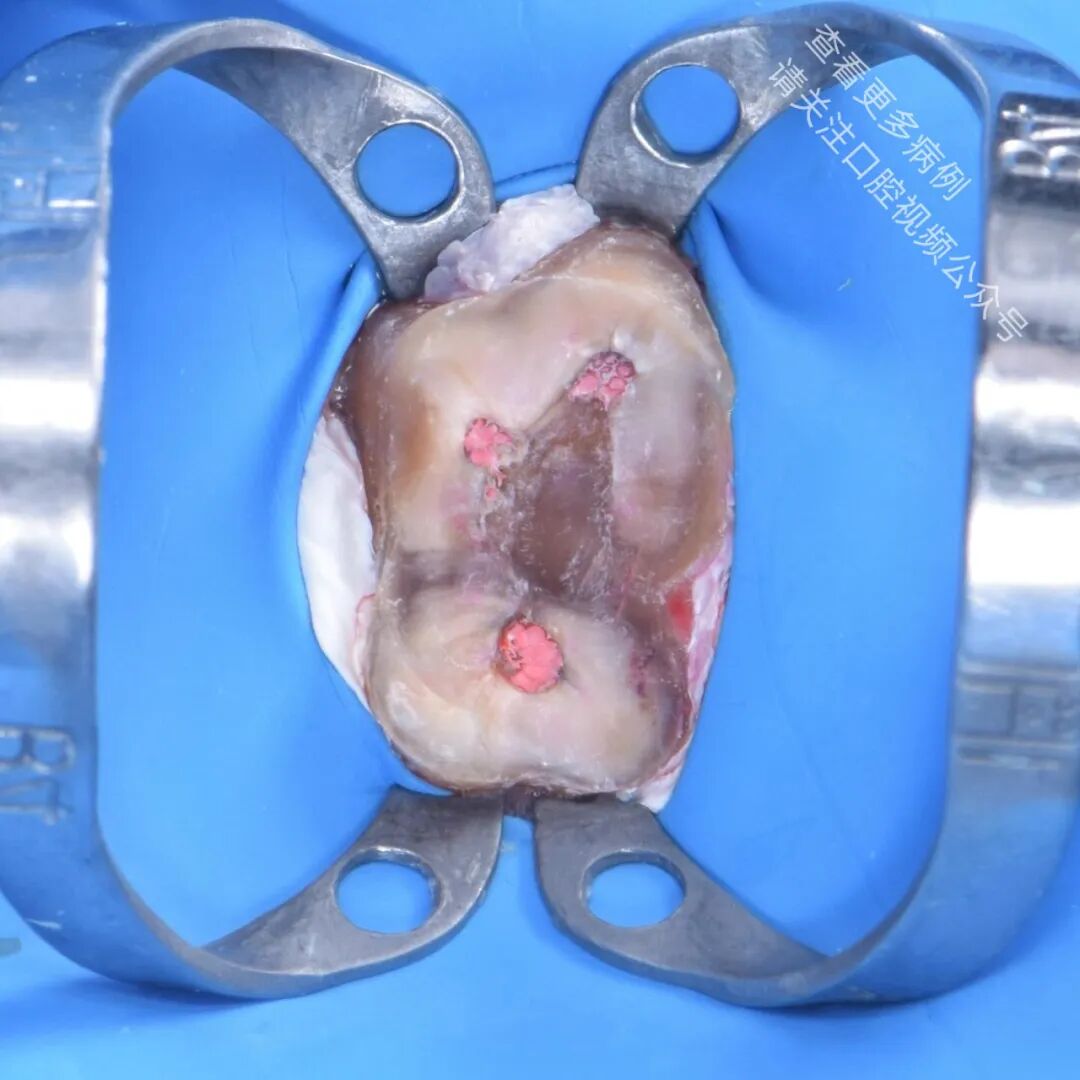

作者按照仿生学原则制作了生物基底层